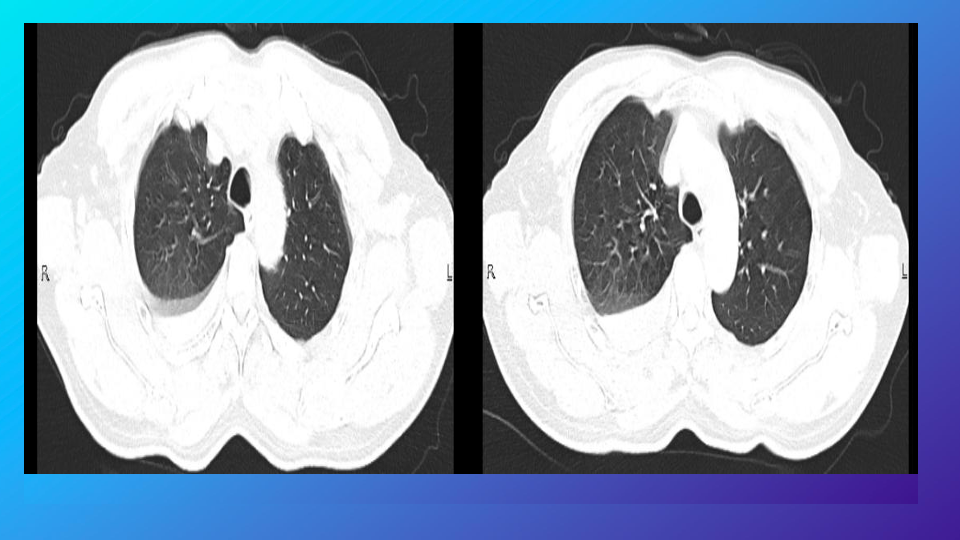

胸部外伤